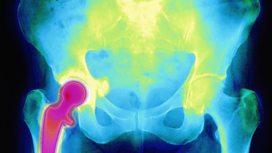

![]() - On Jeremy Vine Today- Jeremy discusses hip replacements, rescue missions, What Makes Us Human and Colombia.

![]() - How long did your hip relacement last?- We speak to a 93-year-old who had his new hip in 1948, when the NHS was created.